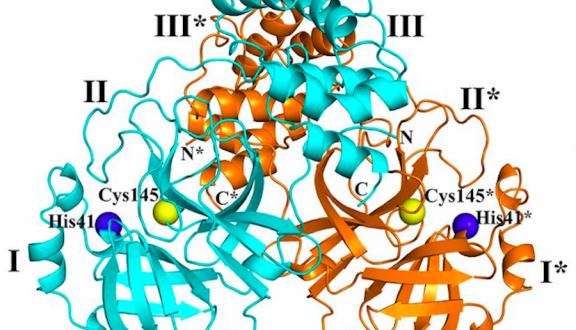

di Guido Poli, Elisa Vicenzi